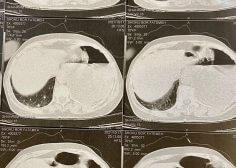

Left pulmonary malignancy and occlusion effect on LPA

Patient with left pulmonary malignancy and occlusion effect on LPA with low LVEF undergone tumor resection and PPM insertion.